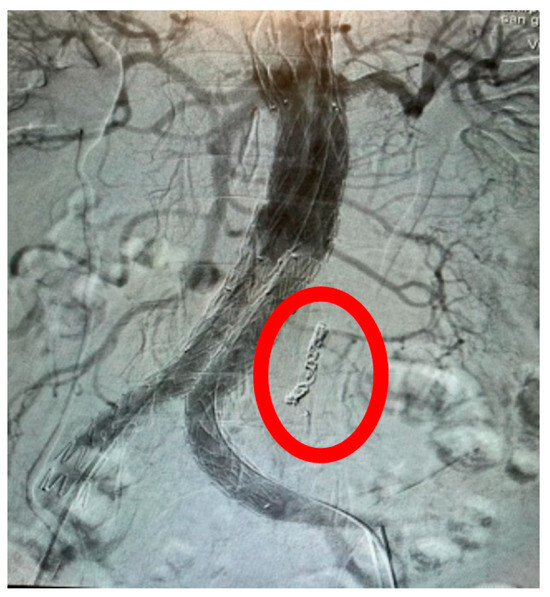

Appendix A.1. Clinical Case 1: Right Renal Visceral Arteriovenous Malformation